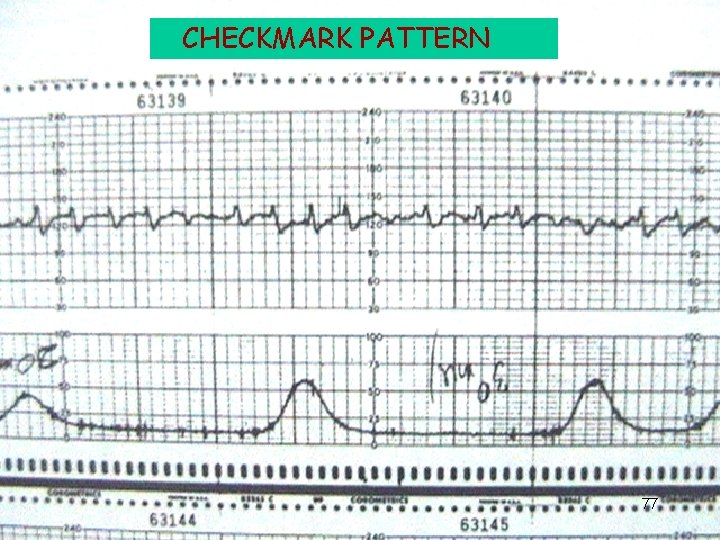

CHECKMARK PATTERN 77